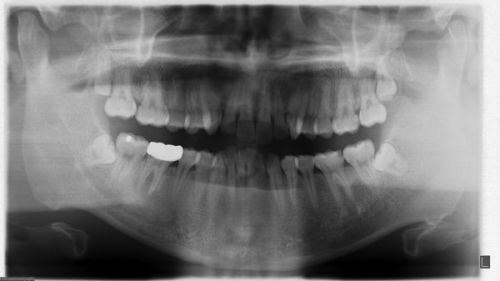

在智齒生長過程中,有些情況下智齒并不需要拔除,以下是不需要拔的智齒圖片及其特點:

1、正常生長的智齒圖片:正常生長的智齒形態正常,與其他牙齒排列整齊,沒有任何不適或并發癥,這類智齒可以像其他牙齒一樣正常發揮咀嚼功能,不需要拔除。

2、輕度阻生智齒圖片:輕度阻生智齒可能只需要進行簡單的正畸治療或局部調整,即可順利生長,這類智齒在治療后可以保留,不需要拔除。

3、無癥狀的阻生智齒圖片:有些阻生智齒雖然存在,但并未引起任何不適或并發癥,這類阻生智齒可以保留,只需定期進行檢查,確保沒有引發其他問題。